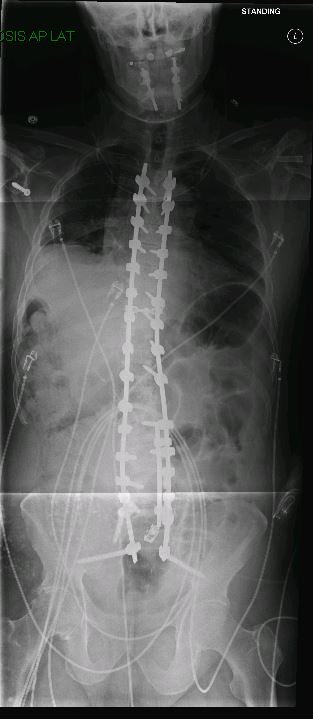

Before & After

Spine Surgery

De-identified imaging from complex spine surgery cases. Each pair shows pre-operative pathology alongside post-operative correction across cervical, lumbar and deformity subspecialties.